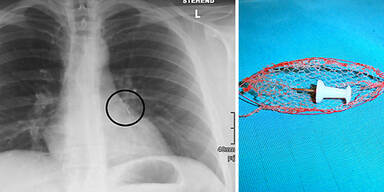

Dort setzte Lungenfacharzt Franz Wimberger mit seinen Kollegen Sebastian Zillinger und Franz Ginterstorfer ein Endoskop ein, an dessen Ende ein Drahtgeflecht befestigt ist. Die Vorrichtung wird üblicherweise dafür verwendet, Fremdkörper aus der Speiseröhre zu holen. Im verästelten Bronchiengeflecht war der Eingriff allerdings wesentlich schwieriger. Nach zwei Stunden gelang es schließlich, die Nadel herauszufischen, ohne weiteren Schaden anzurichten. Wäre das nicht geglückt, hätte sich der 29-Jährige einer heiklen Operation unterziehen müssen. Das Risiko, dass er dabei einen Lungenflügel eingebüßt hätte, wäre groß gewesen.